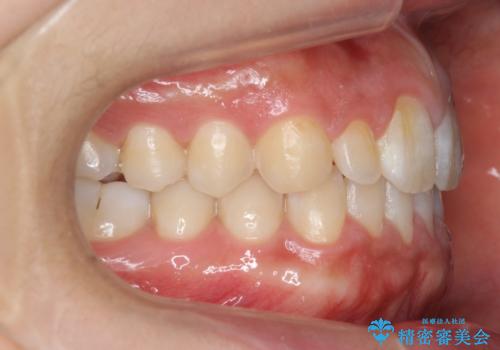

前歯のすきま 矯正治療とセラミックで小さな歯を形良く

- 前歯のすきまを気にして来院。

左上の2番が生まれつき小さく、スペースが余っていました。

右上の2番もやや小さめでしたが、相談の上、左上2番のみセラミックで形を整えることとしました。

そのほかの隙間はマウスピース矯正で閉じることにしました。